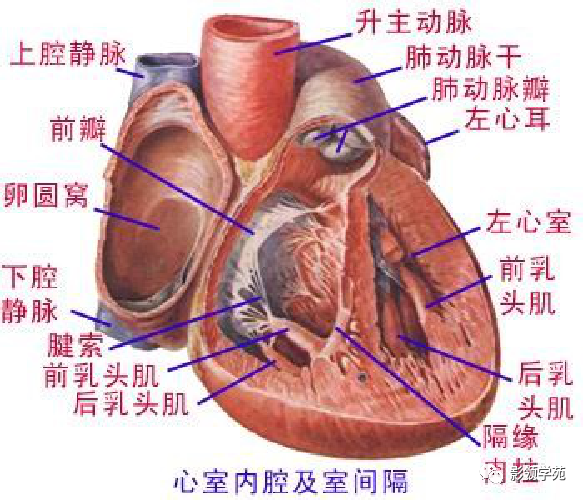

心血管系统

心血管系统